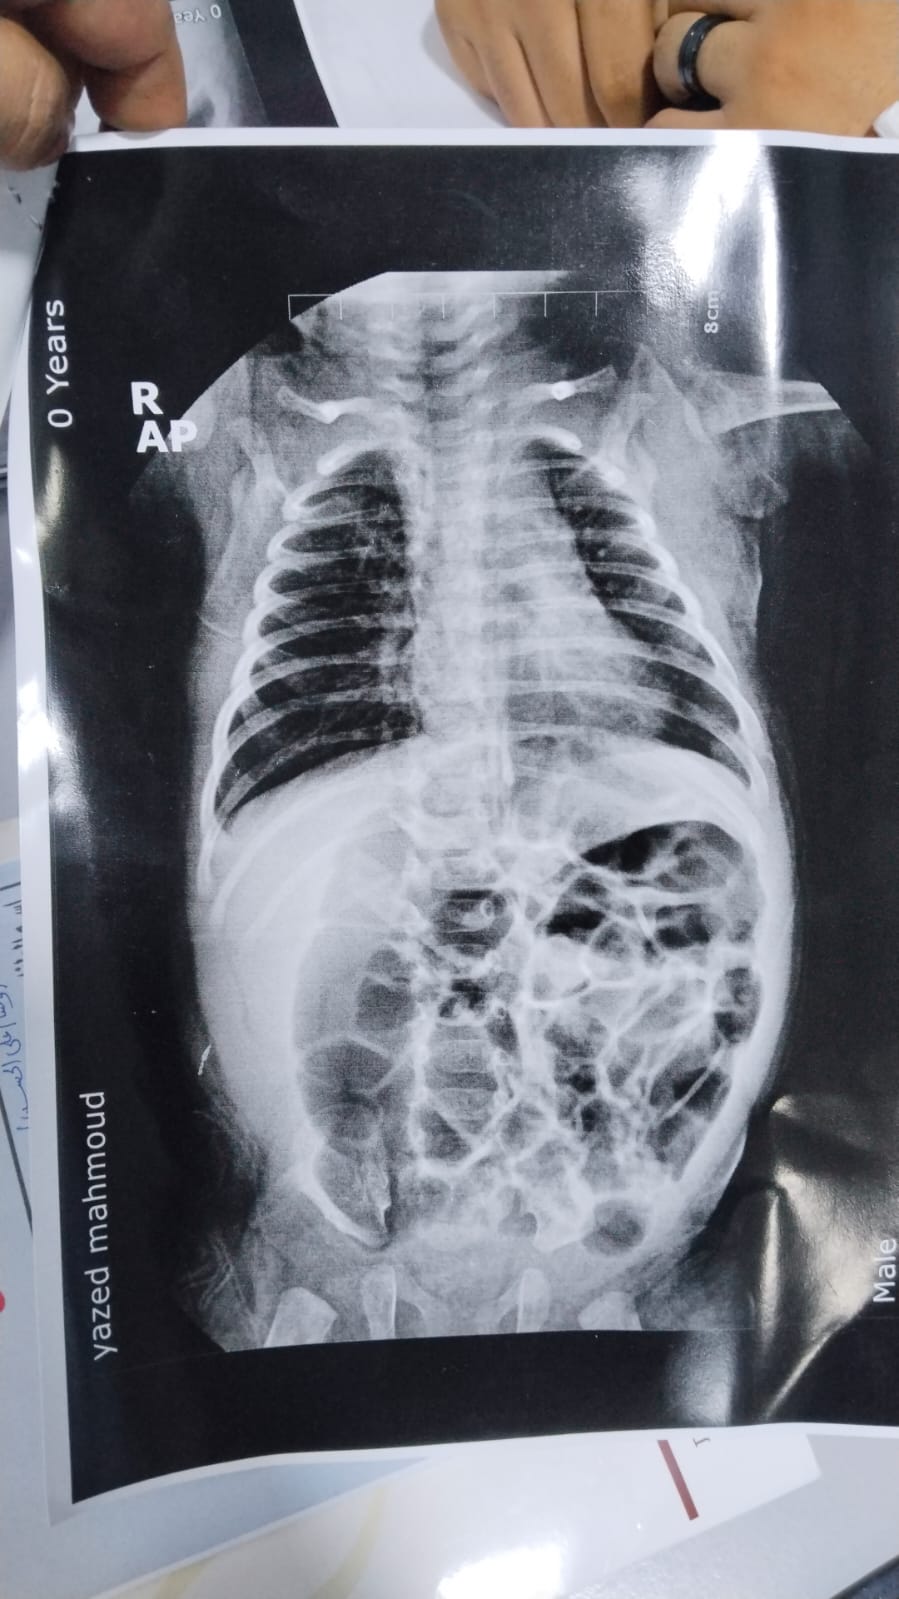

ما تفاصيل هذه الأشعة؟

ممكن قراءة الإشاعة